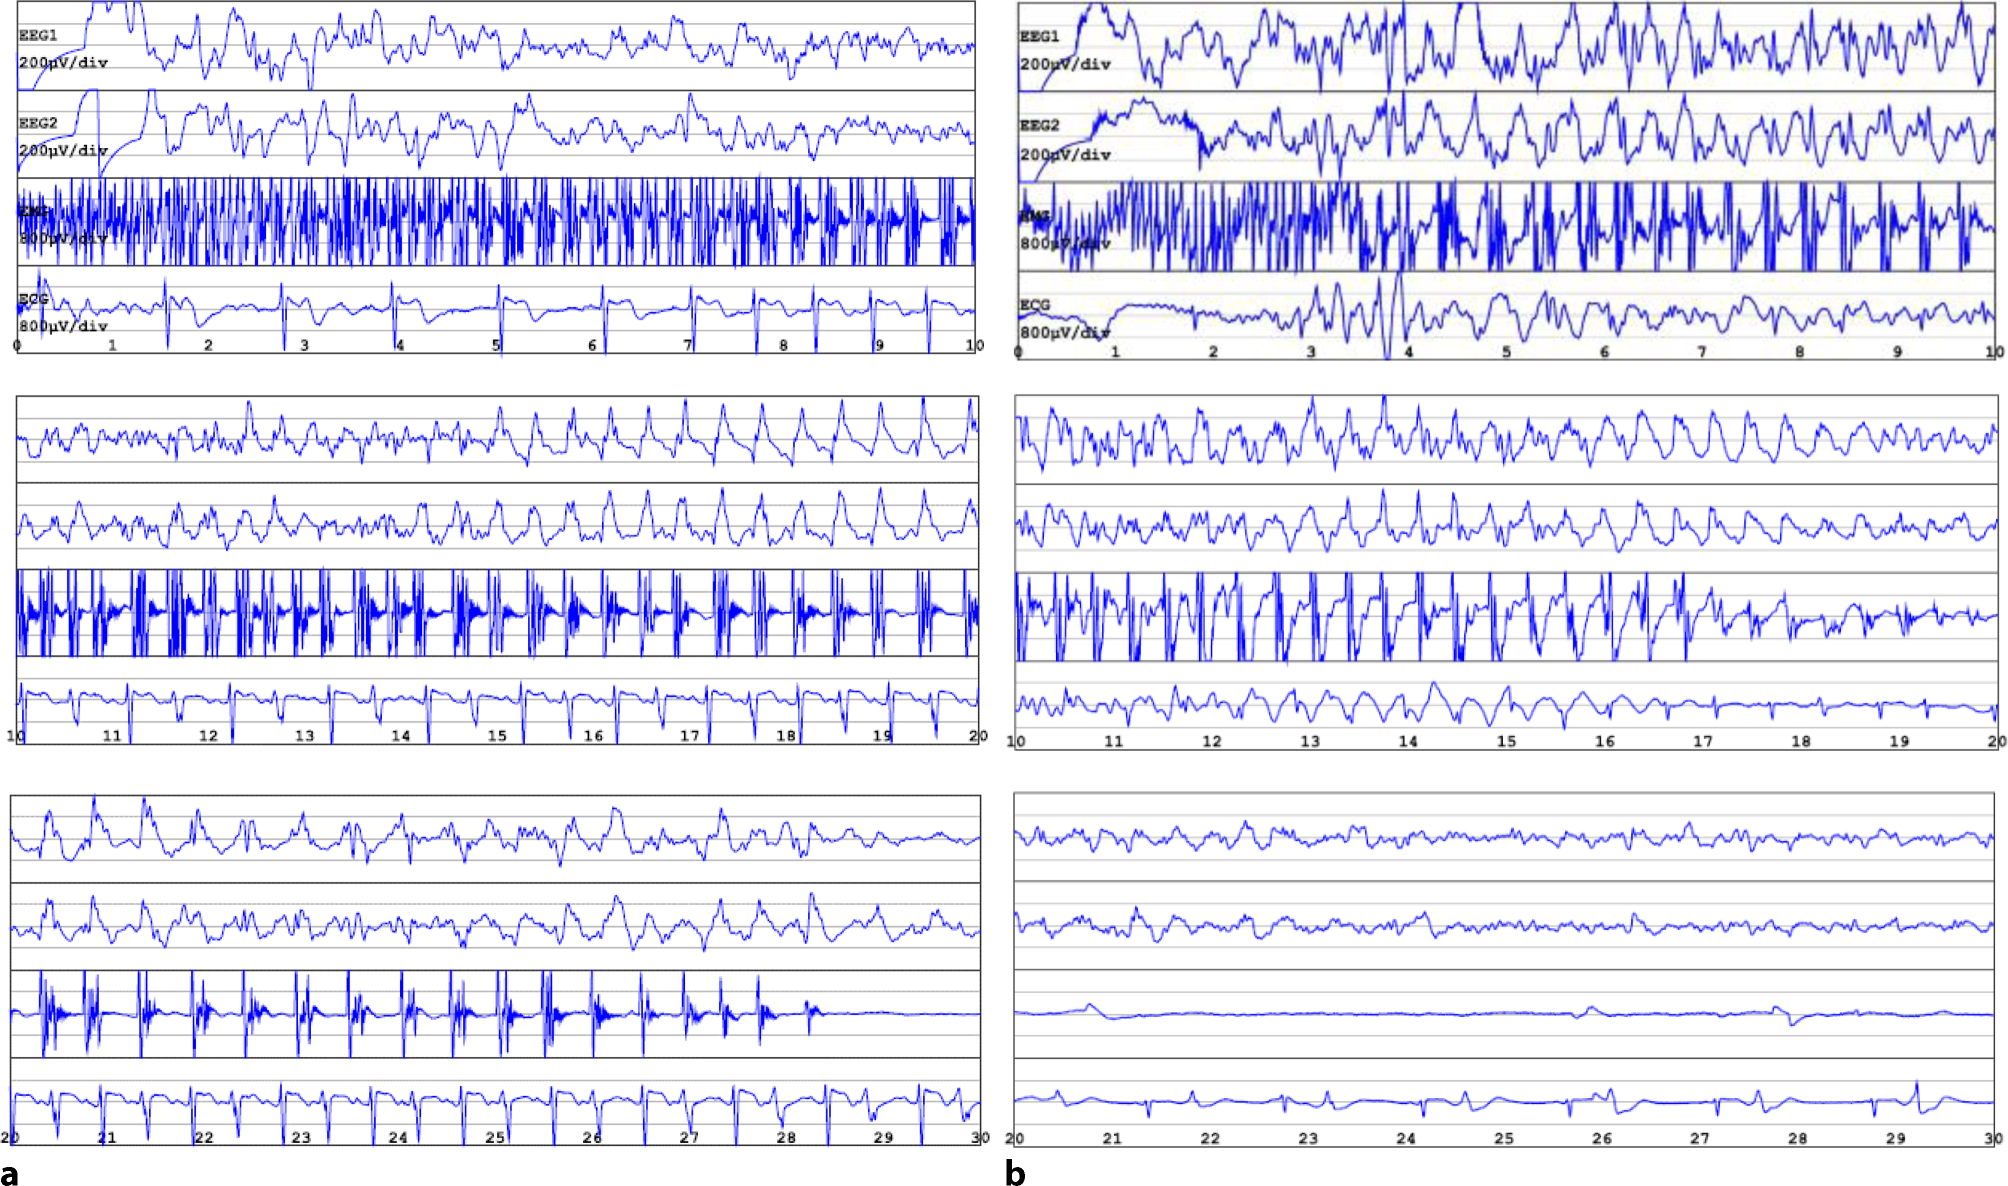

During the spontaneous seizure, recordings of the EEG, ECG, and EMG were collected (Fig. 1a) and exported to GPD (Genie Patient Database; Elektrika Inc.), a software for digital export of ECT data. The patient recovered without complications, without any subjective symptoms or clinical signs suggestive of neurological dysfunction. A follow-up EEG a few hours later revealed a moderate diffuse cerebral dysfunction consistent with the previous epileptic seizure, with occasional diffuse alternating side-emphasized delta/theta activity and intermittently slowed basal rhythm.

Fig. 1

Electroconvulsive therapy (ECT) reports from two different treatment sessions. a Spontaneous generalized tonic-clonic seizure after administration of etomidate, 20 mg: intermittent spike activity on the background of low beta and theta activity turning into spike epileptic activity of low amplitude, slow frequency, and transition to medium amplitude (15 to 20 s), medium frequency, with clear seizure termination (second 29) and poor suppression. b Induced seizure with 140% energy setting and anesthetic thiopental, 400 mg: intermittent spike activity turns into spike epileptic activity of medium amplitude, medium frequency, with less clear seizure termination and poor suppression. EEG 1 and 2 electroencephalogram in right and left channel, respectively. x‑axis time in seconds, y‑axis amplitude in µV. EMG electromyogram. ECG electrocardiogram

The subsequent two ECT treatments, switched back to thiopental 400 mg, showed adequate ECT-induced seizures (Fig. 1b). After 12 treatments, the ECT course was discontinued due to insufficient response, documented by a MADRS score of 21 points, indicating clinical improvement but an inadequate response to ECT. Bupropion XR was increased to 300 mg.